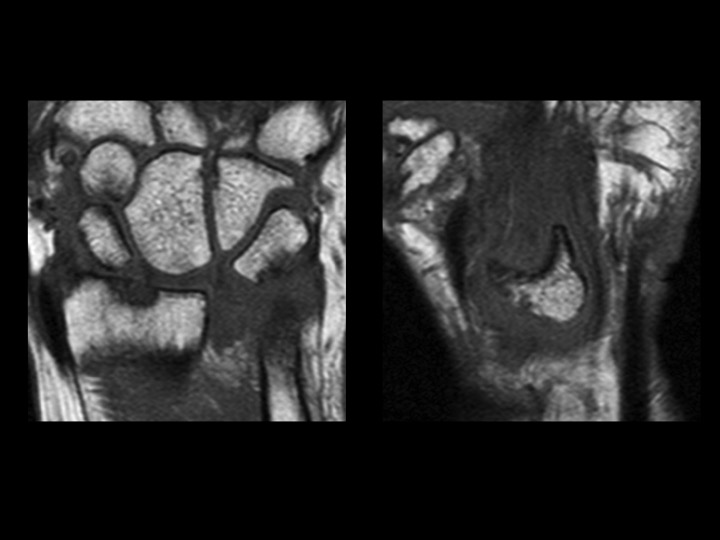

53F 6-8 mos pain with mass in carpal tunnel

What makes this amusing (to me) is that the radiographs (slide 5) were done and reported (by me) 4 days prior to MRI. Patient claims prior work related injury, though this was not the focus of the office visit note. The hand surgeon interpreted the XR in his note as no scapholunate interval widening, no DISI (thats the funny part). MRI was ordered to evaluate mass in the carpal tunnel region. The patient moved a little because she was in alot of pain. The Sag PDFS images show the median nerve being stretched and compressed anterior to the chronically dislocated lunate. (the lunate seems to be happy) Reference article.

Lunate dislocation